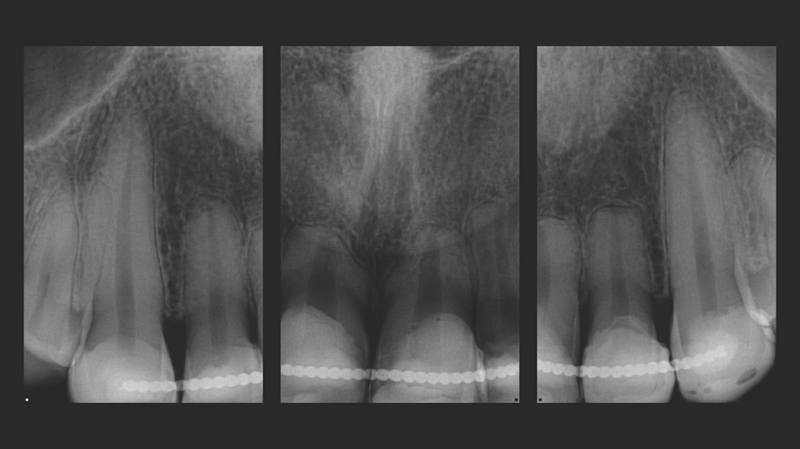

A young woman in her 20s, burdened by the discoloration of her upper anterior teeth from past trauma, came to Dr. Jaleena Fischer-Jessop, DDS, MBA, searching for a solution that would restore her smile. The patient was treated with a conservative and cost-effective solution: no-prep direct-bonded composite veneers. Dr. Fischer-Jessop chose this method to mask the discoloration and match the patient’s upper teeth with the lower anteriors—avoiding the need for more invasive procedures like implants or costly lab processed veneers. The shades B1D and Enamel White (EW) were selected to lighten the teeth and Transcend™ composite’s Universal Body (UB) shade was used to ensure the margin blended naturally into the cervical areas.

- Patient Background: A female patient in her 20s with a history of trauma to her upper anterior teeth. Despite the trauma, the teeth remained stable, so implants were not necessary.